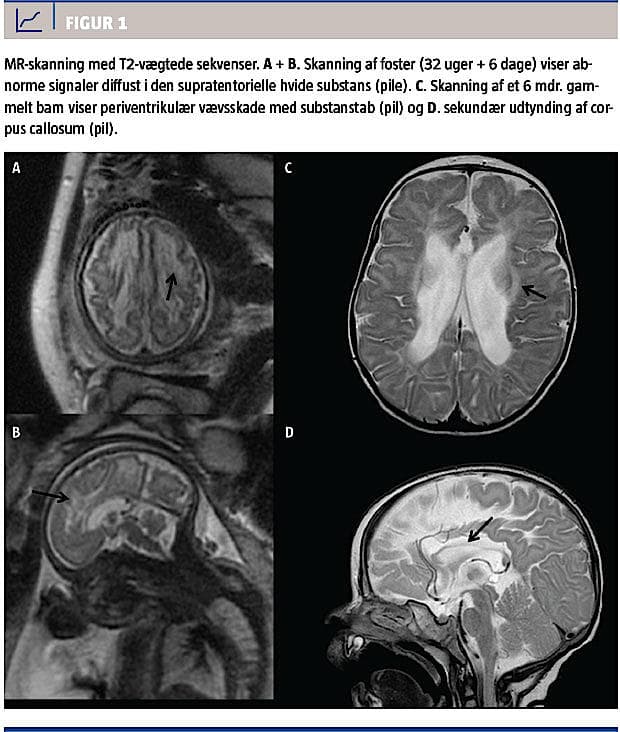

i graviditetsuge 30 + 2 fandtes mistanke om væksthæmning og øget mængde væske cerebralt i de laterale ventrikler. Herefter fulgte et langt forløb med indlæggelser af den gravide kvinde pga. subileus og opkastninger. En MR-skanning i uge 32 + 6 viste diffuse forandringer i den hvide substans periventrikulært i fostrets hjerne (Figur 1). Fødslen blev igangsat i uge 36 + 6 pga. det samlede forløb og mistanken om intrauterin væksthæmning. Fødselsforløbet var ukompliceret, og barnet fik apgarscore 10 efter et minut og efter fem minutter og havde en fødselsvægt på 2.060 g.

Seks måneder gammel blev barnet indlagt pga. tics, skrigeture, manglende hovedkontrol og mistanke om mikrocefali. Man fandt, at barnet havde nedsat bevægelighed i overekstremiteterne, og det greb ikke spontant ud efter ting. En øjenlæge konstaterede, at barnet havde 10% syn på begge øjne. Et EEG viste normale forhold. En MR-skanning af barnets hoved viste et stort ventrikelsystem, glioseforandringer periventrikulært og en meget tynd corpus callosum.